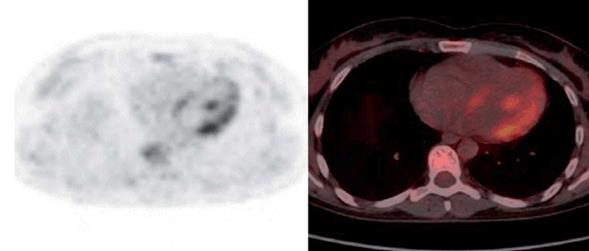

Luego de tres años de realizado el diagnóstico, agrega disnea y palpitaciones; en ECG y Holter presenta taquicardia sinusal. Ecocardiograma normal. DLCO: 138%, CVF: 124%. Se solicita PET/TC por planteo de compromiso miocárdico. RMC no disponible.

El resultado del PET/TC informa: captación heterogénea y parcheada miocárdica compatible con sarcoidosis (figura 5).

Se inicia tratamiento inmunosupresor con metotrexate, evitando la realización de biopsia miocárdica. La evolución de la paciente ha sido favorable a tres años del diagnóstico de SC, sin evidencia de complicaciones cardíacas y con estabilidad respiratoria.